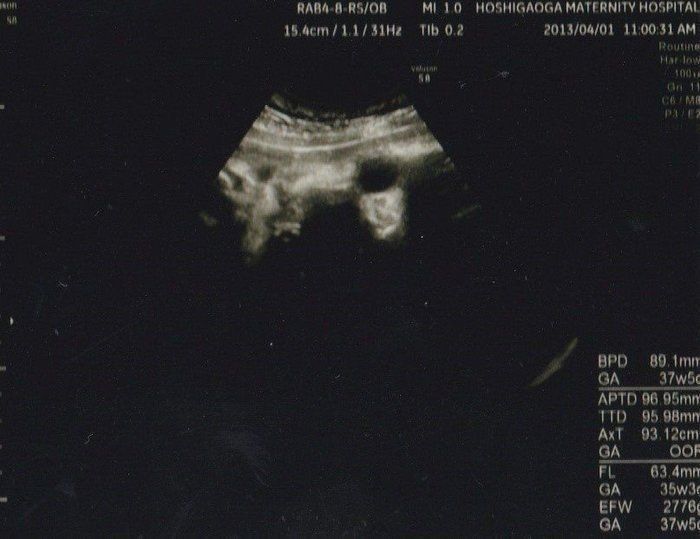

妊娠後期、赤ちゃんが育っていない? エコー写真で振り返る3人目の出産体験 -